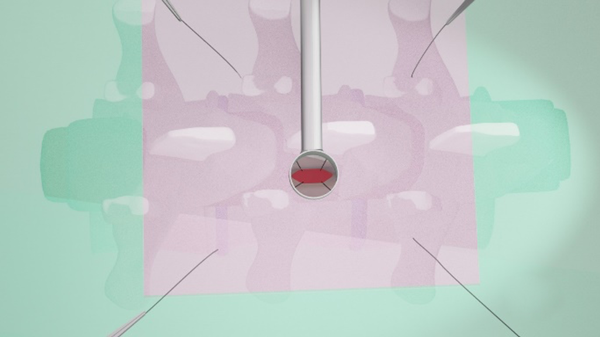

Para describir esta técnica se utilizan las agujas del reloj como referencia posicional, en dónde cefálico es la hora 9 y podálico la hora 3 (fig. 5). Para la retracción dural se requiere de 4 agujas de punción lumbar Nº 19 Gauge enhebradas con suturas de Seda 2.0 (fig. 6). Vamos a tomar como ejemplo un abordaje tubular percutáneo izquierdo en donde el cirujano se posiciona en la hora 6 y el ayudante en la hora 12. Dicho esto, tras la exposición dural luego de una hemilaminectomia, se coloca la primera aguja en hora 5, aproximadamente a 5 cm por fuera del sistema tubular y se punza en dirección del abordaje. Mediante visión microscópica se ve la aparición de la punta de la aguja en el campo quirúrgico, y se toma un extremo de la Seda 2.0 el cual se saca a través del tubo (extremo A), y el otro extremo de la sutura emerge por el sitio de punción tras la extracción de la aguja (extremo B). Ambos extremos se sujetan con una pinza de reparo. Se realiza el mismo procedimiento en hora 7. Del lado medial vamos a tener a las apófisis espinosas como obstáculo, por lo que no hay una constante en el sitio de entrada de las agujas. Puede intentarse introducirlas en horas 11 y 1 desde el lado contralateral, y que pasen por el espacio interespinoso, o bien por horas 10 y 2 desde el mismo lado del abordaje. Con las 4 Sedas 2.0 reparadas, se procede a la apertura dural en forma longitudinal, intentando preservar la aracnoides. Se realiza un punto en el reborde dural de hora 5 con Seda 4.0 y ambos extremos se anudarán con el extremo A de la seda 2.0 correspondiente. Luego de esto se toma el extremo B y se tracciona hasta conseguir que la Seda 4.0 emerja por piel y se fija con la pinza de reparo al campo quirúrgico. Esto último hace que podamos darle mayor o menor tensión a la retracción dural según sea conveniente. Luego se harán los restantes puntos durales de retracción repitiendo la técnica, para así dar comienzo a la etapa de resección tumoral.

Cuando ya se encuentran en tracción los 4 puntos de reparo dural, los extremos de la incisión se aproximan entre sí, y eso permite incidir con bisturí dichos extremos para realizar una nueva tracción de los puntos de reparo, y así, una mayor exposición lateral (Fig. 7, 8 y 9).

Fig. 9: Exposición del contenido intradural mediante retracción dural percutánea.